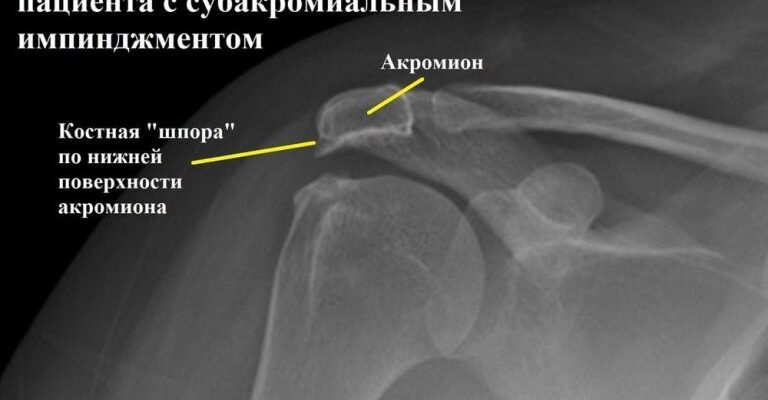

Діагностика: Коли слід звернутися до лікаря